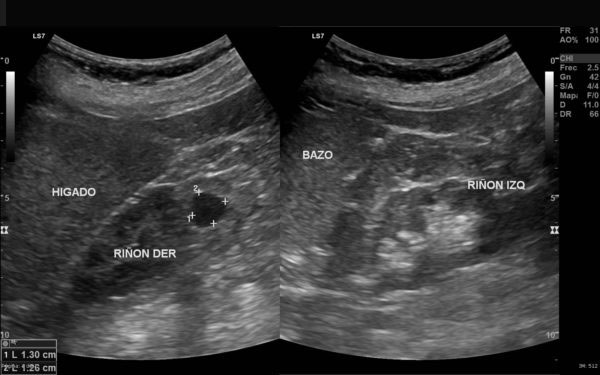

La ecografía es una técnica de diagnóstico por imagen no invasiva que utiliza ondas de ultrasonido para visualizar en tiempo real órganos, tejidos blandos y estructuras internas del cuerpo. A diferencia de otros estudios, no emplea radiación, lo que la convierte en una herramienta segura, ampliamente utilizada en diversas áreas médicas para detectar alteraciones, monitorear enfermedades y apoyar decisiones clínicas con agilidad y precisión.

En SCANNER S.A. contamos con equipos ecográficos de alta resolución, diseñados para ofrecer imágenes claras y detalladas. Nuestro servicio incluye tanto ecografía general como ecografía especializada, permitiendo realizar estudios abdominales, pélvicos, ginecológicos, obstétricos, renales, tiroideos, de partes blandas, musculoesqueléticos y más.